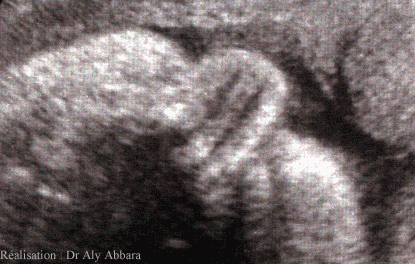

Nez fœtal en coupe transversale montrant

la cloison et les cavités nasales